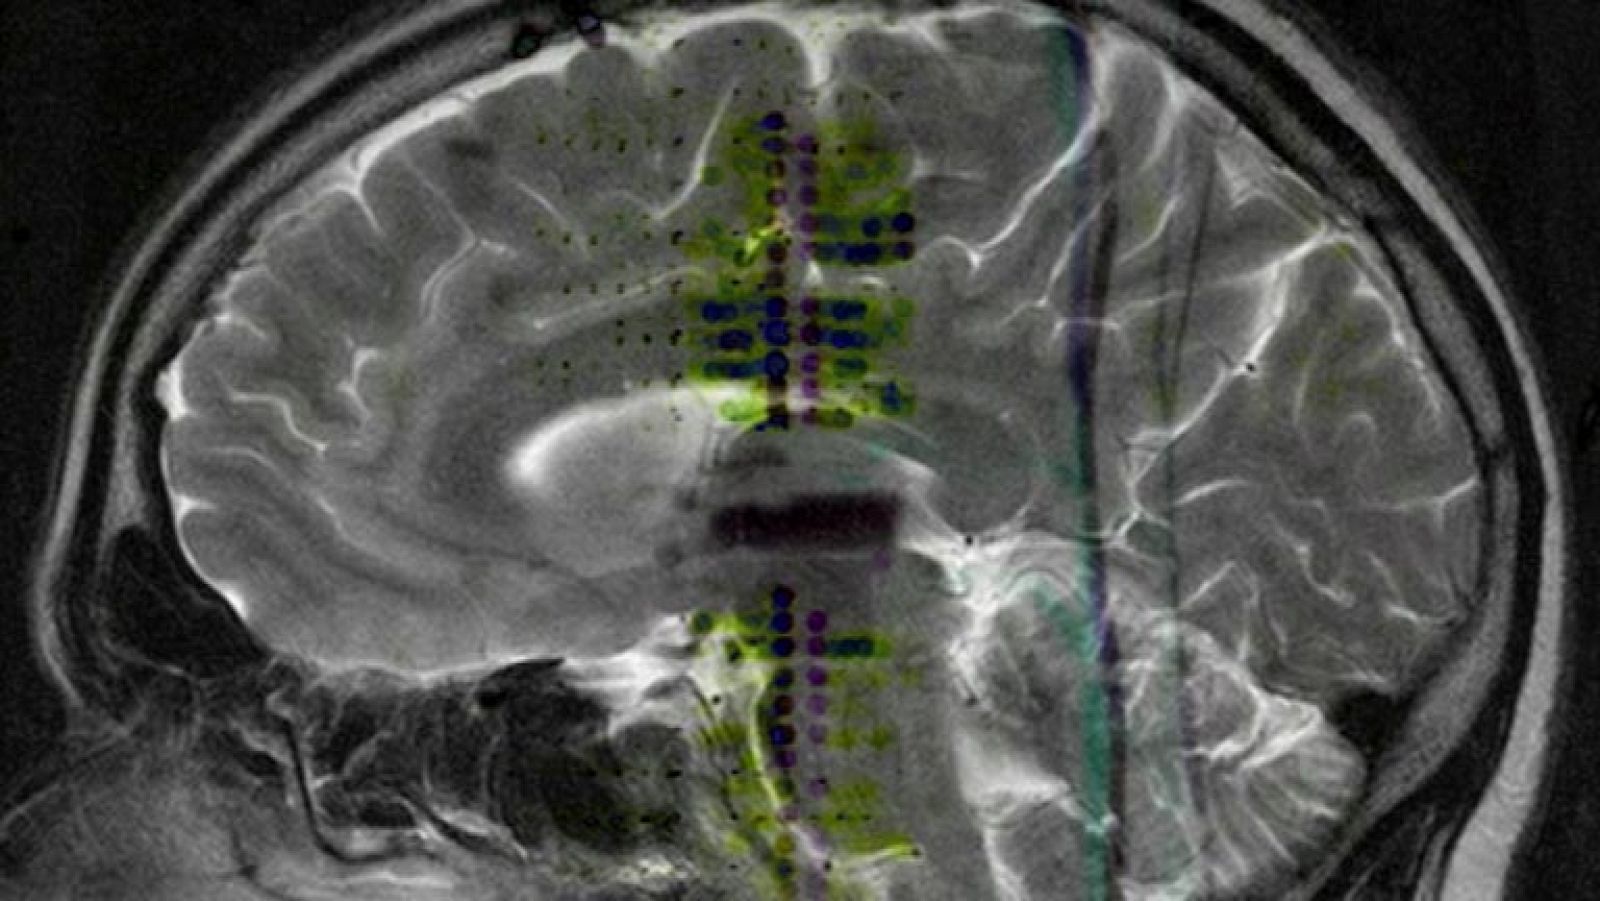

La migraña, cuarta enfermedad que causa más discapacidad

La migraña, la sufren más de tres millones y medio de españoles y en los casos más graves puede ser muy invalidante. Según la Organización Mundial...